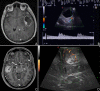

Introduction: Glioma surgery is aimed at obtaining maximal safe tumor resection while preserving or improving patient's neurological status. For this reason, there is growing interest for intra-operative imaging in neuro-oncological surgery. Intra-operative ultrasound (ioUS) provides the surgeon with real-time, anatomical and functional information. Despite this, in neurosurgery ioUS mainly relies only on gray-scale brightness mode (B-mode). Many other ultrasound imaging modalities, such as Fusion Imaging with pre-operative acquired magnetic resonance imaging (MRI), Doppler modes, Contrast Enhanced Ultrasound (CEUS), and elastosonography have been developed and have been extensively used in other organs. Although these modalities offer valuable real-time intra-operative information, so far their usage during neurosurgical procedures is still limited. Purpose: To present an US-based multimodal approach for image-guidance in glioma surgery, highlighting the different features of advanced US modalities: fusion imaging with pre-operative acquired MRI for Virtual Navigation, B-mode, Doppler (power-, color-, spectral-), CEUS, and elastosonography. Methods: We describe, in a step-by-step fashion, the applications of the most relevant advanced US modalities during different stages of surgery and their implications for surgical decision-making. Each US modality is illustrated from a technical standpoint and its application during glioma surgery is discussed. Results: B-mode offers dynamic morphological information, which can be further implemented with fusion imaging to improve image understanding and orientation. Doppler imaging permits to evaluate anatomy and function of the vascular tree. CEUS allows to perform a real-time angiosonography, providing valuable information in regards of parenchyma and tumor vascularization and perfusion. This facilitates tumor detection and surgical strategy, also allowing to characterize tumor grade and to identify residual tumor. Elastosonography is a promising tool able to better define tumor margins, parenchymal infiltration, tumor consistency and permitting differentiation of high grade and low grade lesions. Conclusions: Multimodal ioUS represents a valuable tool for glioma surgery being highly informative, rapid, repeatable, and real-time. It is able to differentiate low grade from high grade tumors and to provide the surgeon with relevant information for surgical decision-making. ioUS could be integrated with other intra-operative imaging and functional approaches in a synergistic manner to offer the best image guidance for each patient.